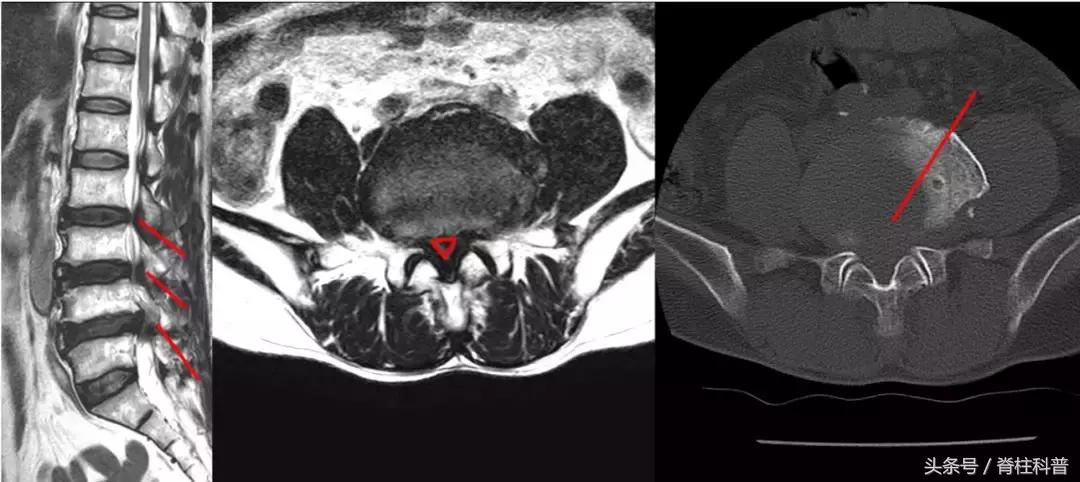

腰腿痛部分相关疾病图示

腰椎管狭窄症

峡部裂

椎管内肿瘤